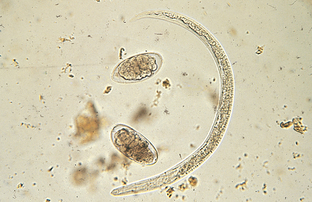

Strongyloides stercoralis and Strongyloides tumefaciens are often referred to as “intestinal threadworms.” These nematodes are unique; only a parthenogenetic female (female that can lay eggs without copulation with a male) is parasitic in the host. Parasitic males do not exist. These females produce eggs, but in dogs these eggs hatch in the intestine, releasing first-stage larvae. Figure 6-7 shows the parasitic adult females, eggs, and first-stage larvae of Strongyloides species. The larvae are 280 to 310 μm long and have a rhabditiform (club-shaped) esophagus, with a club-shaped cranial corpus, a narrow median isthmus, and a caudal bulb. The prepatent period is 8 to 14 days.

Figure 6-7 Parasitic adult females, eggs, and first-stage larvae of Strongyloides species. These larvae are 280 to 310 μm long and have a rhabditiform esophagus, with a club-shaped cranial corpus, a narrow median isthmus, and a caudal bulb. (Reprinted from Hendrix CM, Robinson E: Diagnostic parasitology for veterinary technicians, ed 3, St Louis, 2006, Mosby.)